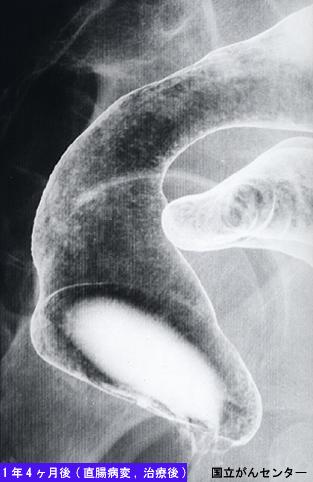

疾病(病理主体)的分类恶性淋巴系肿瘤/恶性淋巴瘤

部位(按器官分)大肠/直肠

检查方法X线